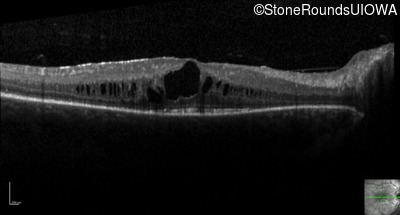

Optical Coherence Tomography - Right - 20/30 -2

Exemplar / OCT Stack